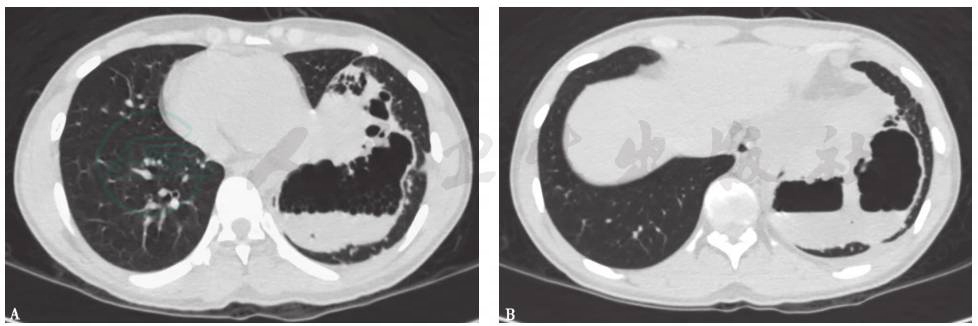

胸部CT(发病第14天):左肺下叶高密度影,边界欠清晰,其间可见多发囊性病变(图2)。

图2 发病第14天胸部CT表现

胸部CT:左肺下叶病灶边界较为清楚,表现为实变、空洞,空腔病灶内有液平(图13),其脓液界面呈类蜂窝状气囊影改变。

图13 入院后胸部CT表现(发病后37天)